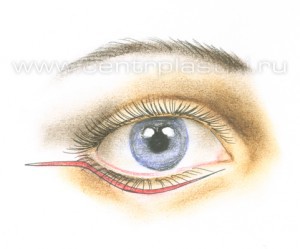

Рис. 5 Подтяжка средней зоны лица обычно выполняется под наркозом. Среднее время операции 1,5-2 часа. Разрез кожи и мышцы выполняется под ресничным краем нижнего века. Рис. 6.

Рис. 6 Мышцу, аккуратно приподнимают и отделяют до края глазницы. Рис.7. Жировые «грыжи» опускаются вниз за край глазницы и фиксируются к надкостнице несколькими нитями, Рис. 8-9 таким образом, удается заполнить слезную и веко-щечную борозды Рис. 10.